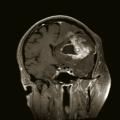

Une tumeur cérébrale peut se compliquer d’une hémorragie, favorisée par des facteurs intrinsèques à la tumeur (la néoangiogenèse tumorale dans les gliomes malins ; certaines métastases cérébrales sont plus volontiers hémorragiques, en particulier celles des mélanomes), ainsi que des facteurs systémiques (troubles de la coagulation induits par la tumeur, thrombopénie, anticoagulation à visée curative pour une phlébite ou une embolie pulmonaire, thérapies anti-angiogéniques). L’hémorragie intratumorale peut se manifester par une hypertension intracrânienne, un déficit focal d’installation aiguë ou la majoration d’un déficit déjà connu, une crise d’épilepsie. Elle peut être aussi asymptomatique et diagnostiquée à l’imagerie. Elle apparaît au scanner non injecté sous la forme d’une hyperdensité spontanée et à l’IRM non injectée par un hypersignal en T1 (fig. 8) et en hyposignal en T2* au sein de la tumeur.